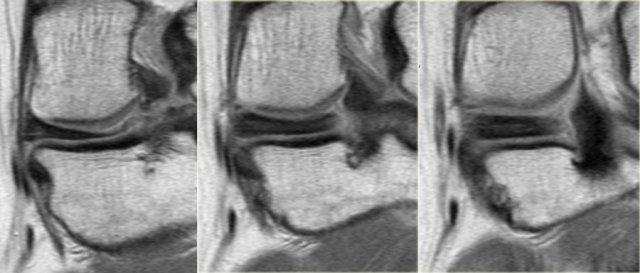

Hãy quan sát hình ảnh bên trái và cố gắng xác định vấn đề của sụn chêm này là gì.

Sau đó tiếp tục xem các hình ảnh liên tiếp tiếp theo của cùng bệnh nhân này.

Như bạn đã đoán được qua tiêu đề của đoạn này, đây là một trường hợp sụn chêm lật (flipped meniscus).

Sụn chêm lật là một dạng đặc biệt của rách dạng quai xô (bucket-handle tear).

Sụn chêm lật xảy ra khi mảnh vỡ của sừng sau bị lật ra phía trước, khiến sừng trước của sụn chêm có vẻ to hơn bình thường.

- Thân sụn chêm ngoài.

- Sừng sau quá nhỏ và sừng trước có vẻ to hơn với đường viền không đều.

- Thoạt nhìn có vẻ như có một đường rách dọc ở sừng trước, nhưng thực chất phần sau của cấu trúc này chính là phần lật của sừng sau bị rách.

Cấu trúc phía trước là sừng trước.

Cũng cần lưu ý tình trạng phù tủy xương khu trú và dấu ấn lõm sụn khớp. - Cấu trúc phía trước là sừng trước.

- Một số bất thường ở phần sau.

- Phần sau di chuyển về phía đuôi (caudal).

- Trong hố gian lồi cầu là điểm nối giữa mảnh di lệch và phần còn lại của sừng sau.